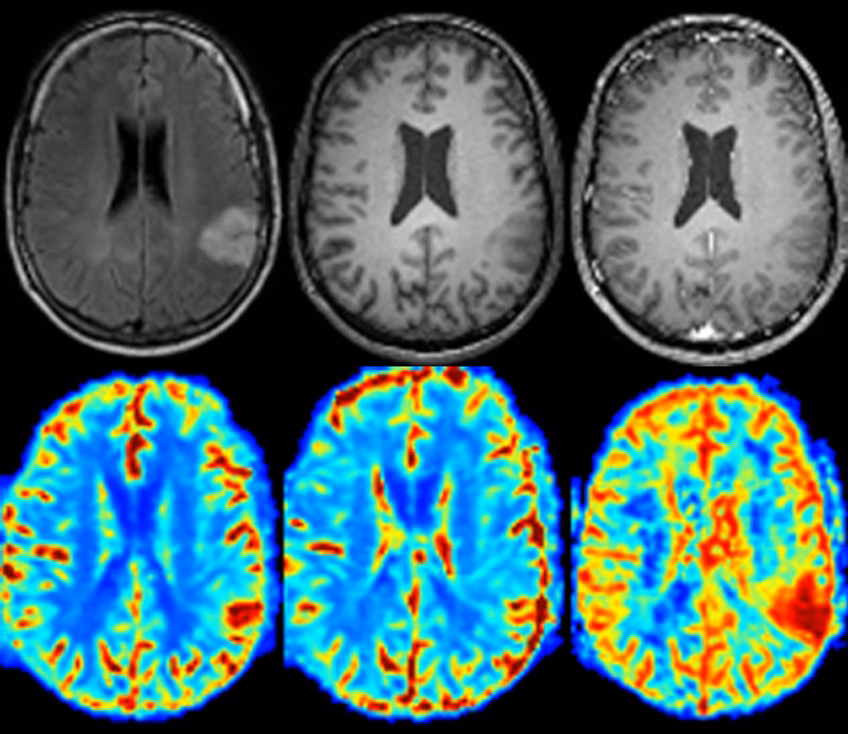

- Tumores y Lesiones: Es excelente para detectar y caracterizar tumores en el cerebro, la médula espinal, órganos internos y tejidos blandos. Permite diferenciar entre tejidos sanos y anormales, y ayuda a determinar la extensión de la enfermedad, incluido el cáncer.

- Trastornos Neurológicos: La IRM cerebral es fundamental para diagnosticar accidentes cerebrovasculares (ictus), tumores cerebrales, esclerosis múltiple, aneurismas, lesiones de la médula espinal y otras afecciones del sistema nervioso central.